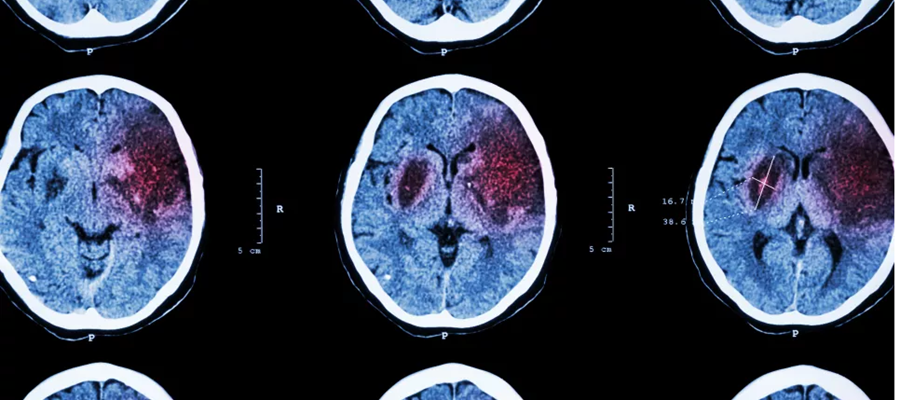

Personer som drabbas av en TIA eller stroke till följd av kraftig förträngning i den främre halspulsådern, så kallad karotissubocklusion, löper stor risk att återinsjukna. Det visar en ny avhandling vid Umeå universitet. Det kan påverka hur strokepatienter med svåra kärlförändringar bör handläggas i framtiden.

I sin avhandling har Thomas Gu studerat karotisstenos, en förträngning i halspulsådern som ofta ses hos äldre och som utgör en viktig riskfaktor för ischemisk stroke som är den vanligaste typen av stroke. Hans forskning har riktat särskilt fokus mot patienter med den mest uttalade formen där kärlet nästan kollapsar efter förträngningen, ett tillstånd benämnt karotissubocklusion.

Trots det är tillståndet svårt att upptäcka. När forskargruppen undersökte diagnostiken med datortomografiangiografi, DTA, som är den vanligaste metoden i klinisk praxis, visade det sig att endast omkring en femtedel av fallen identifierades korrekt. Många tolkades felaktigt som vanlig stenos eller total ocklusion, vilket riskerar att vilseleda behandlande läkare.